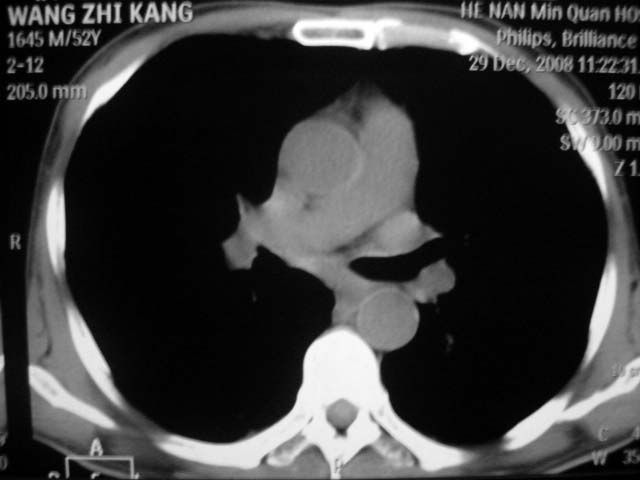

男,52岁,发热2月,糖尿病史。

抗结核治疗irpz方案,血糖未治疗,空腹15.9左右。症状无好转,左胸痛。

复查ct

2、双肺见多发片状及结节状高密度影,大多数病灶中心均见“空泡征”。

3、纵隔内淋巴结肿大。

结果:两肺继发性肺结核并曲霉菌感染。